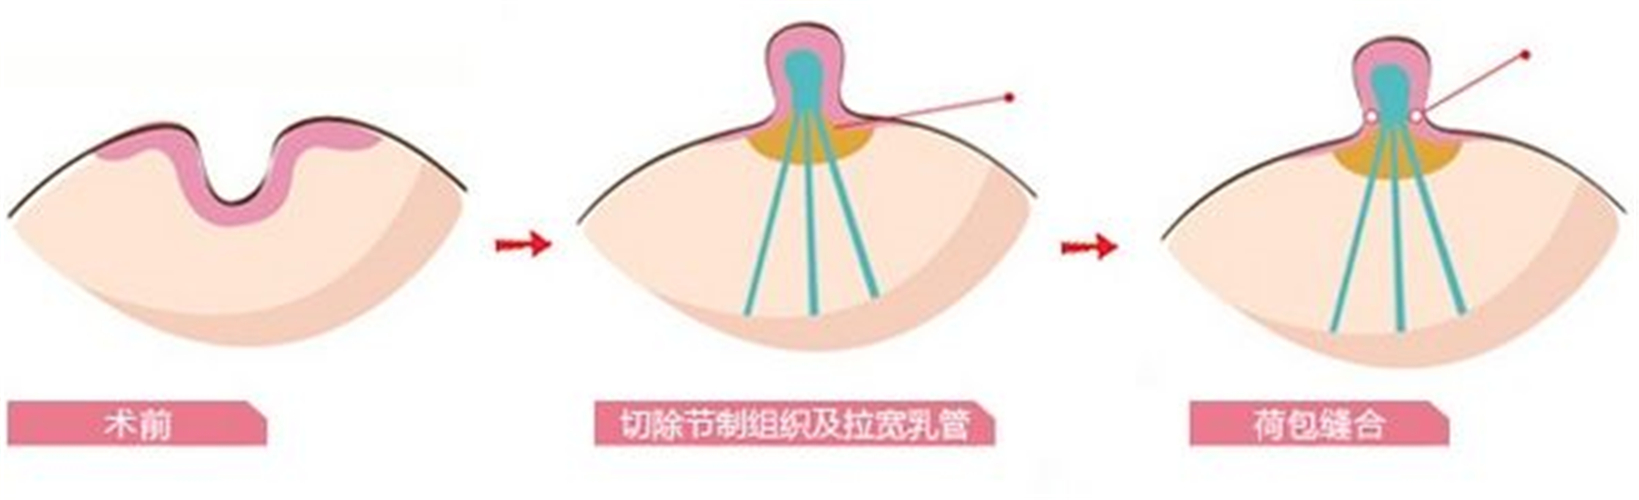

A:想要解決乳頭內陷,為避免誘發乳腺炎等疾病,建議儘早行手術治療。通過手術的方式,將患者的乳頭環狀括約肌切開,然後重新進行縫合矯正。在手術中應注意保護好患者的乳腺導管,效果一般較好。若患者有手術的相關禁忌症或不願意進行手術,也可進行局部乳頭……